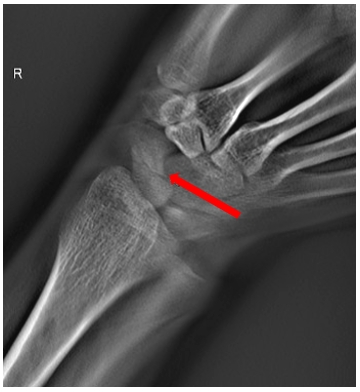

病例二:女,31岁。右手摔伤。

通过断层融合图像分析,为豆状骨骨折。